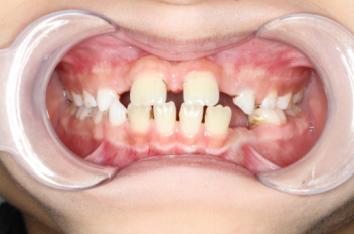

❸ 牙齿不齐:影响咬合关系,影响美观。

前

后